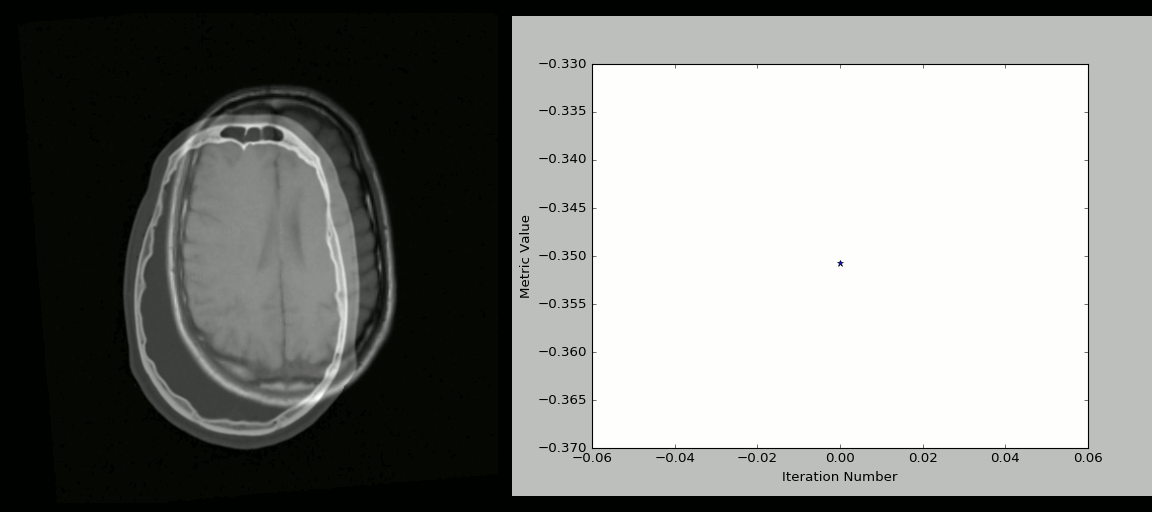

8、SimpleITK

ITK(Insight Segmentation and Registration Toolkit)是一个为开发者提供普适性图像分析功能的开源、跨平台工具套件,SimpleITK 则是基于 ITK 构建出来的一个简化层,旨在促进 ITK 在快速原型设计、教育、解释语言中的应用。SimpleITK 作为一个图像分析工具包,它也带有大量的组件,可以支持常规的滤波、图像分割、图像配准registration功能。尽管 SimpleITK 使用 C++ 编写,但它也支持包括 Python 在内的大部分编程语言。

有很多 Jupyter Notebooks 用例可以展示 SimpleITK 在教育和科研领域中的应用,通过这些用例可以看到如何使用 Python 和 R 利用 SimpleITK 来实现交互式图像分析。

示例

使用 Python + SimpleITK 实现的 CT/MR 图像配准过程:

SimpleITK animation